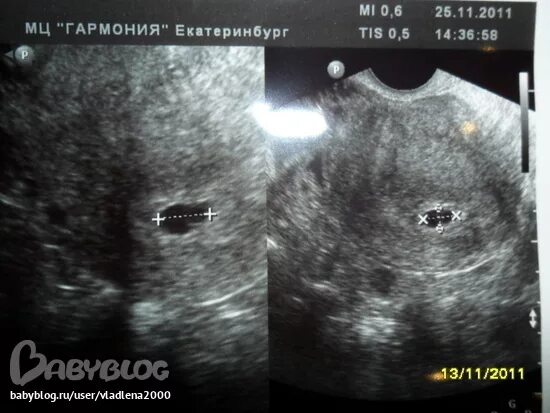

Плодное яйцо видно при хгч